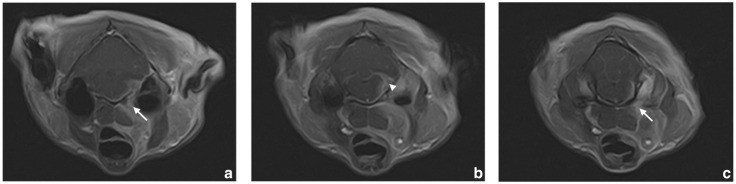

Case summary: A 12-year-old male castrated domestic shorthair cat exhibited right Horner's syndrome, right facial nerve paresis, difficulty swallowing, coughing, gait abnormalities and weight loss. Despite prior unspecific treatment by a primary care veterinarian with cortisone and antibiotics, the cat's condition worsened, culminating in tetraparesis and right hemispasms. Imaging studies, including CT and MRI, identified a mass extending from the carotid body into the neurocranium, causing displacement of adjacent brain structures and meningeal contrast uptake. Histopathology confirmed a malignant B-cell lymphoma. Differential diagnoses are explored, with a particular focus on carotid body tumours, which originate from the chief cells of the carotid body. These neoplasias are rare in non-human primates, dogs, cats and horses, possibly influenced by genetic predisposition and environmental factors such as hypoxia.